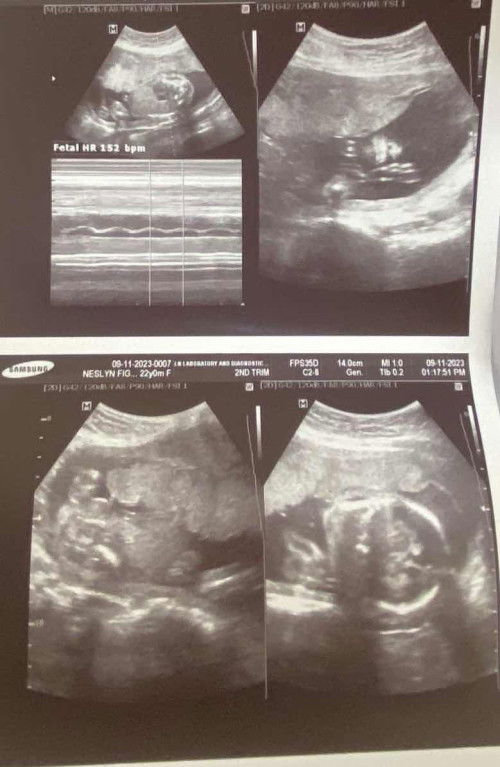

Ultrasound @20 weeks and 3 days